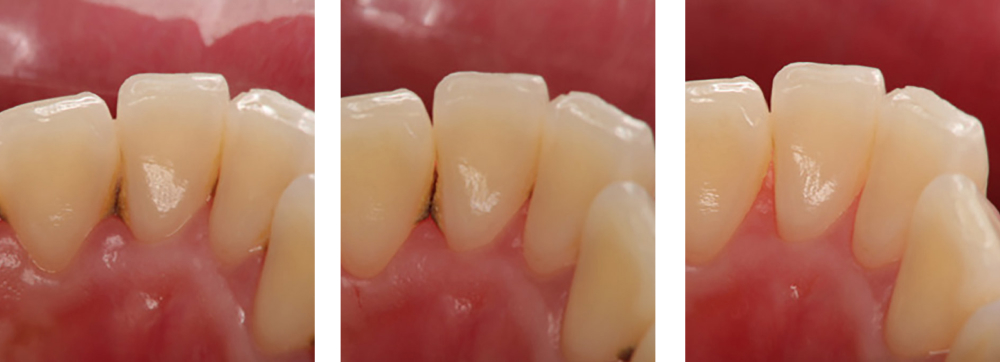

小児歯科

術前

術後

| 治療内容 | 外傷による歯冠破折に対してCRにて破折片の再接着を行った |

|---|---|

| 治療期間・回数 | 1日・1回 |

| 費用 | 保険適用となります |